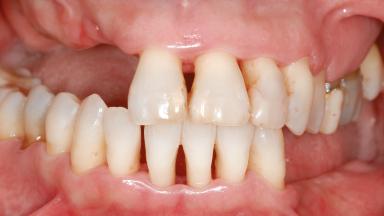

Shell Technique for Horizontal and Vertical Maxillary Bone Augmentation in a Partially Edentulous Patient with Aggressive Periodontal Disease

A 46-year-old woman was referred for treatment whose main complaints were mobility of her fixed partial dentures (right maxilla and left mandible) and periodontal bleeding during function. She also reported having taken systemic antibiotics to treat recurrent swelling in the area of the upper left molars. The patient had not seen a dentist for at least 2 years. She did not smoke and had no history of major systemic disease other than two minor orthopedic procedures some years back. The first-visit examination revealed poor plaque control, tooth mobility, periodontal disease, and a residual dentition widely associated with deep periodontal pockets.

Prosthesis Type FDP